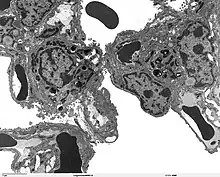

The protein encoded by this gene (SP-A2) is primarily synthesized in lung alveolar type II cells, as part of a complex of lipids and proteins known as pulmonary surfactant. The function of this complex is to reduce surface tension in the alveolus and prevent collapse during expiration. The protein component of surfactant helps in the modulation of the innate immune response, and inflammatory processes.[5]

Surfactant homeostasis is critical for breathing (and thus survival) in the prematurely born infant, but also for maintaining lung health, and normal lung function throughout life. Quantitative and/or qualitative alterations in surfactant composition and/or function are associated with respiratory diseases.[9][10][11][12]

- Maintaining the structure of tubular myelin (an extracellular form of surfactant)